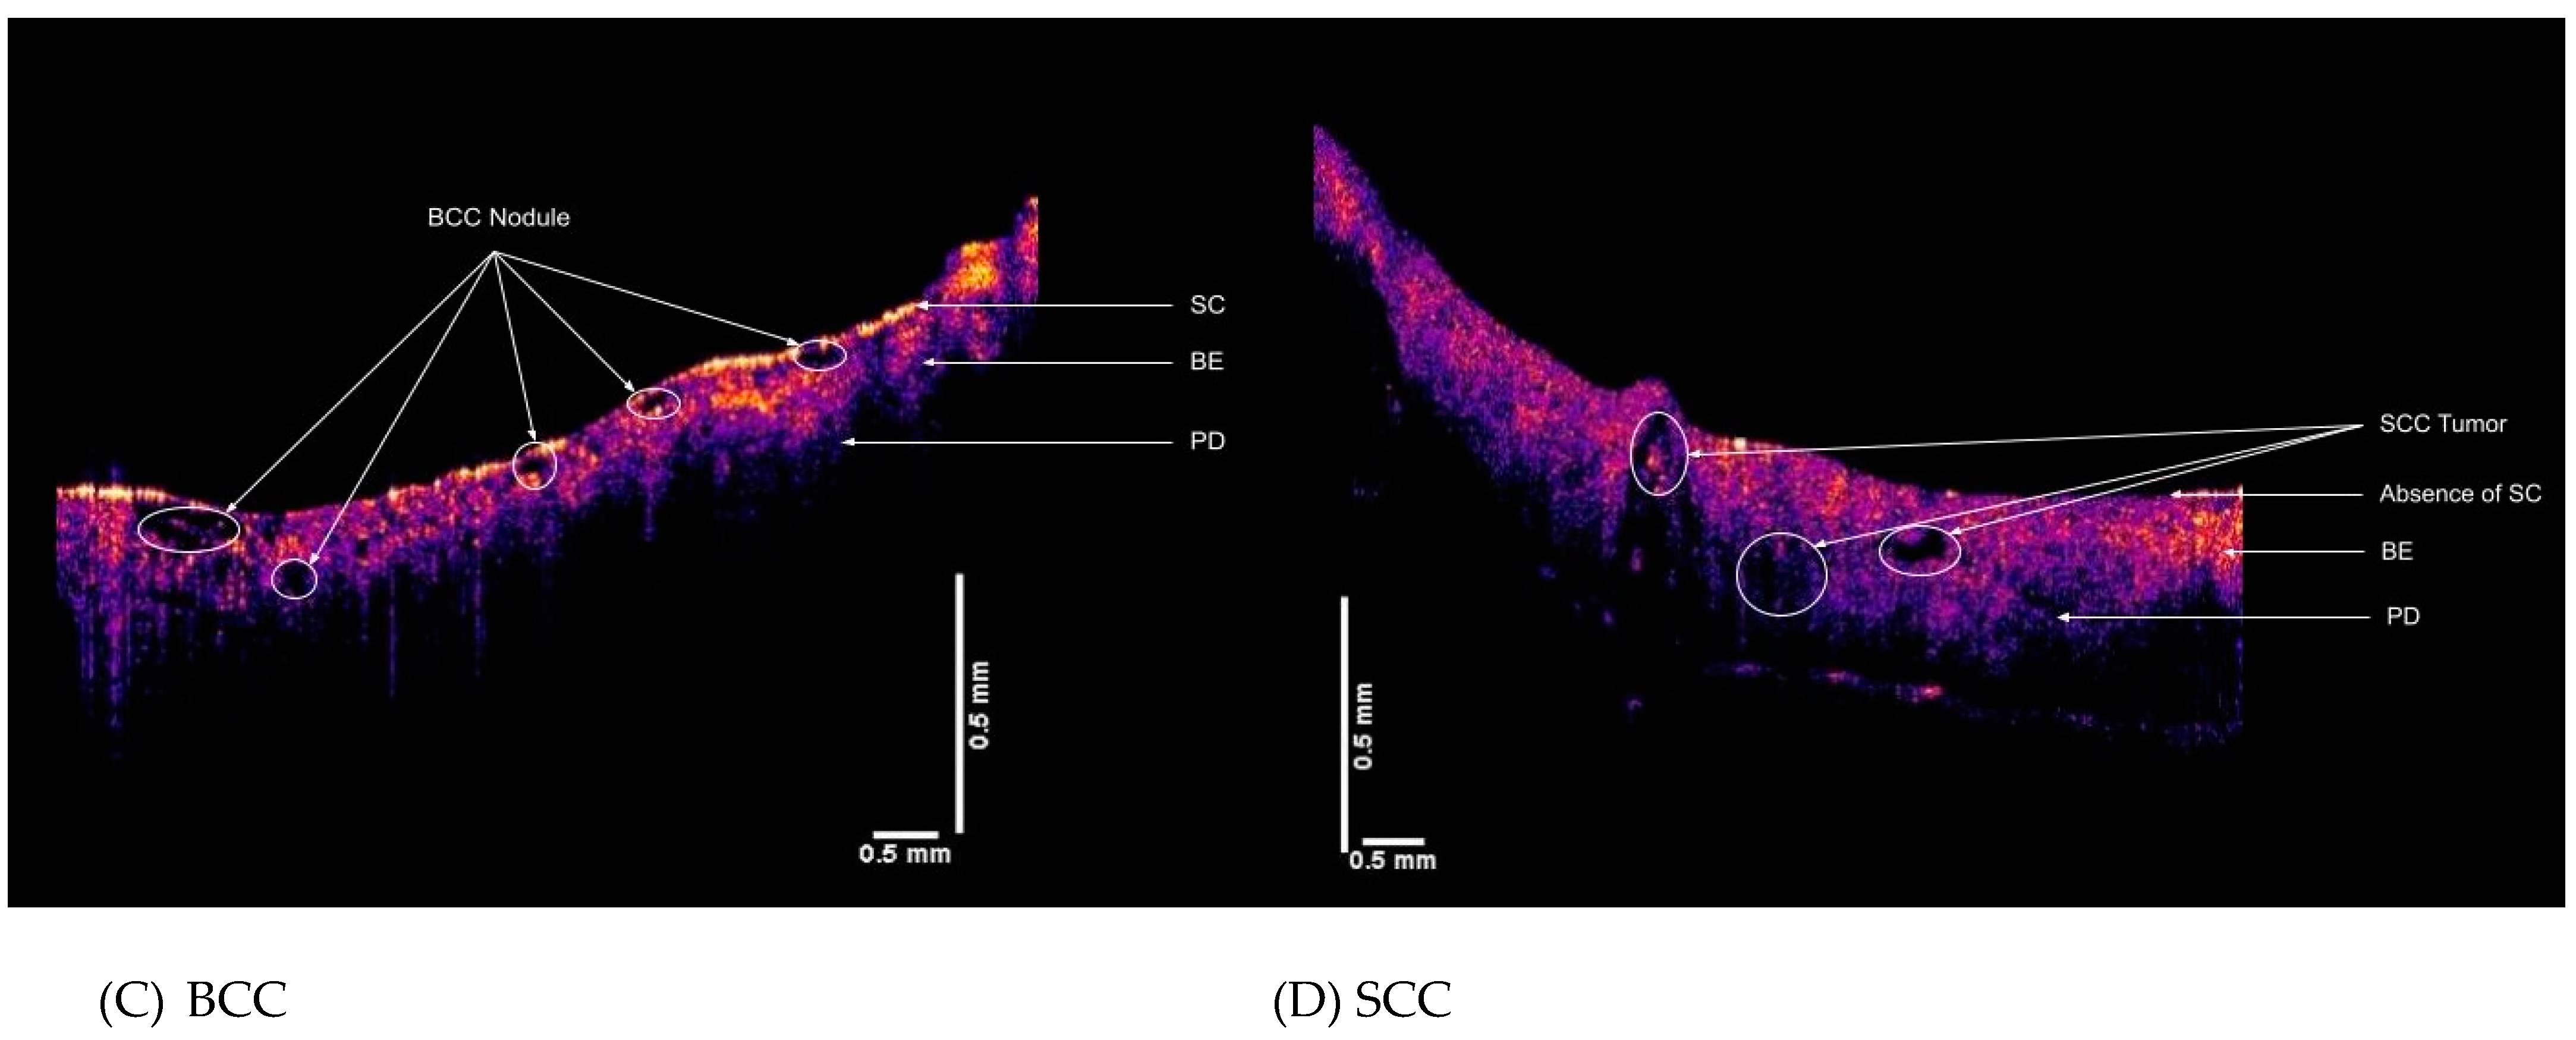

2.2. OCT Images and Scans of Pixel Intensity Versus Depth Measurements

3. Results

4. Discussion

4.1. The 80 Hz Peak

4.2. The 130 Hz Peak

4.3. The 260 Hz Peak